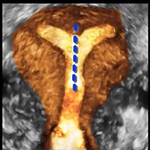

3D Bild eines perfekt sitzenden IUBTM-Kupferperlenballs.

Man sieht die relativ dünne Muskulatur am oberen Ende der Höhle (hier würde eine Kupferkette z.B. nicht verankert werden können). Auch fällt auf, dass die Höhle nur die 15mm Durchmesser "zur Verfügung" stellt. (Die kleinste herkömmliche Spirale braucht fast doppelt so viel Platz).

Gleiches Bild zum vereinfachten Verständnis. Kupferperlen liegen in der Mitte der Gebärmutterhöhle. Der Gebärmutterkanal ist aufgehellt. Die Gebärmuttermuskulatur ist in der Originalfarbe geblieben. Das umliegende Gewebe (im wesentlichen Darmschlingen) ist grau.